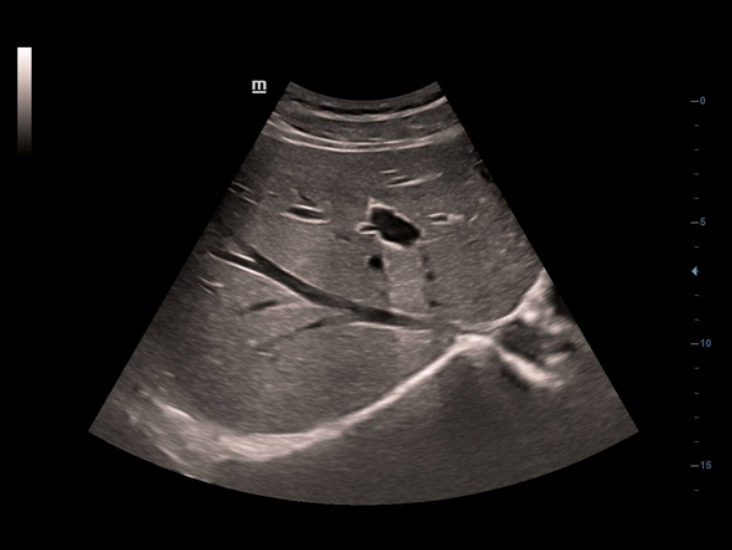

"Full HD" Ăš una soluzione all'avanguardia in grado di soddisfare le esigenze dei professionisti che si intendono garantire un eccellente servizio di assistenza sanitaria di base. Oggigiorno, un sistema a ultrasuoni deve essere in grado di fornire immagini chiare e sia intuitivo e affidabile che, anche in condizioni non ottimali, il sistema a ultrasuoni sia in grado.

Come primo prodotto della gamma "Full HD", DC-40 con Full HD Ăš la risposta perfetta a qualsiasi necessitĂ clinica. Il concetto di "Full HD" Ăš fornire agli utenti funzionalitĂ eccezionali, tra cui una migliore definizione delle immagini, design ergonomico ottimizzato e una maggiore affidabilitĂ .

Con l'applicazione delle tecnologie di imaging tradizionali, migrate da sistemi a ultrasuoni consolidati, DC-40 con Full HD offre immagini di qualitĂ estremamente dettagliate.

Con una combinazione versatile di trasduttori, DC-40 con Full HD offre le migliori prestazioni equilibrate in una vasta gamma di applicazioni e garantisce immagini di qualitĂ per tipologie diverse di pazienti.

DC-40 con Full HD offre una gamma di strumenti in grado di massimizzare l'accuratezza diagnostica con praticitĂ . DC-40 con Full HD puĂČ essere utilizzato in diagnostica per immagini generale, ginecologia/ostetricia e cardiologia e costituisce una soluzione completa per le applicazioni cliniche tradizionali, con un flusso di lavoro semplificato per il massimo dell'efficienza.